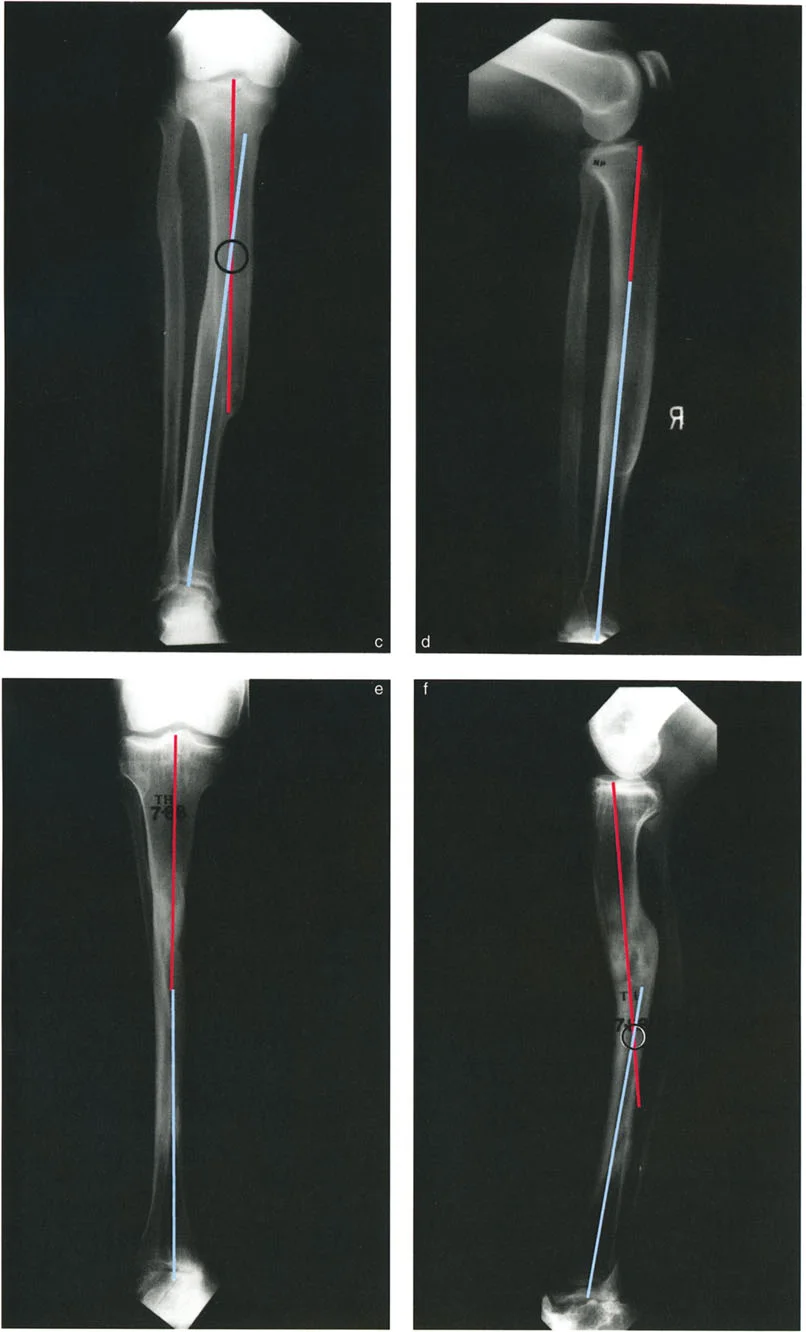

2. التصوير الشعاعي المتقدم:

تُعد الأشعة السينية هي الأداة الأساسية لتشخيص هذه التشوهات، ولكنها تتطلب تقنيات خاصة:

-

الأشعة السينية الكاملة للطرف (Full-Length Standing X-rays):

- يتم التقاط هذه الأشعة للمريض وهو واقف لتحمل الوزن، وتشمل العظم المصاب بالكامل بالإضافة إلى المفصلين أعلاه وأسفله (مثل الورك والركبة والكاحل للساق).

- تُؤخذ هذه الأشعة في وضعين رئيسيين: الأمامي الخلفي (AP) والجانبي (Lateral).

- أهميتها: تسمح هذه الصور للدكتور هطيف بتقييم المحور الميكانيكي للطرف بالكامل وتحديد مدى انحرافه، وقياس زوايا الانحراف وحجم الانزياح بدقة.

بمجرد الحصول على صور التصوير الشعاعي عالية الجودة، يقوم الأستاذ الدكتور محمد هطيف بإجراء تحليل هندسي دقيق باستخدام مبادئ الدكتور بالي:

- رسم المحاور: يتم رسم خطوط المحور الوسطي للعظم (mid-diaphyseal axis lines) للأجزاء القريبة والبعيدة من العظم المصاب على كل من الأشعة السينية الأمامية الخلفية والجانبية.

- تحديد مركز دوران الانحراف (CORA) أو نقطة الانحراف-الانزياح (a-t point): هذه هي النقطة التي تتقاطع عندها خطوط المحور، وتُعد "القمة الحقيقية" للتشوه. تحديدها بدقة أمر بالغ الأهمية لتخطيط مكان قطع العظم.

- قياس الانحراف والانزياح: تُستخدم قياسات دقيقة لتحديد حجم الزاوية (الانحراف) ومقدار التحرك الجانبي (الانزياح).

- تقييم انحراف المحور الميكانيكي (MAD): يُحسب مدى انحراف المحور الميكانيكي عن مركزه الطبيعي في الركبة.